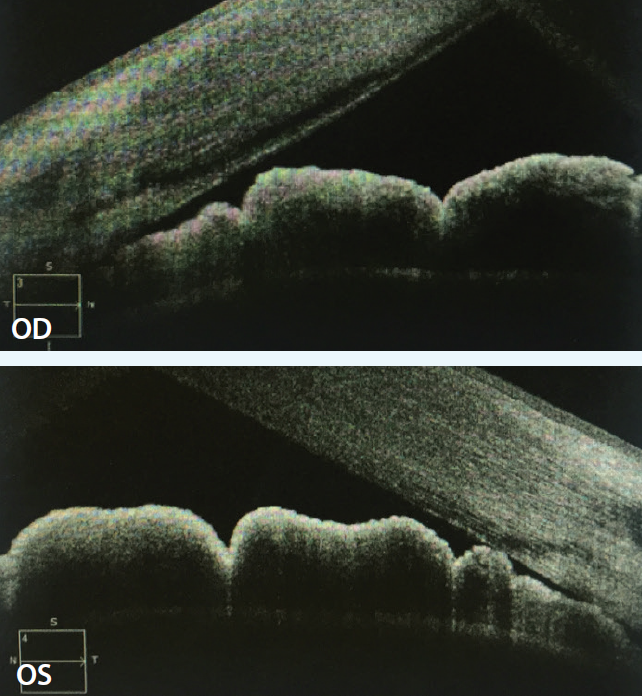

Standard automated perimetry by Swedish Interactive Thresholding Algorithm (SITA) testing demonstrated preserved field in the right eye and a cecocentral defect in the left eye. Ultrasound biomicroscopy (UBM; Figure 2) demonstrated cystic areas within and around the ciliary body, shallow anterior chambers with closed angles, and a plateau iris configuration in both eyes. Peripheral iridotomy was patent in the right eye and not visualized in the left. Anterior segment OCT (Figure 3) demonstrated closed angles consistent with gonioscopy and UBM findings.

Figure 2. UBM demonstrated cystic areas within and around the ciliary body, shallow anterior chambers with closed angles, and a plateau iris configuration in both eyes.

On UBM, iridociliary cysts are thin walled and have sonolucent interiors, as in our case.4,5 Given that the location of these cysts is typically at the iridociliary junction,4 a convex configuration of the angle is created, leading to plateau iris syndrome. If iridociliary cysts cover more than 180º of the iris surface,4 they can cause secondary ACG.